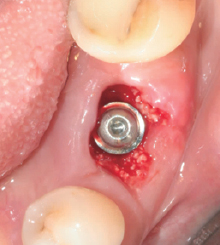

Wifi-Mesh와 BOSS Screw를 이용한 수직 골 증대

① 치조골량 부족으로 Implant 식립 불가

② BOSS Screw 중앙에 고정

③ 골이식 시행

④ Cover를 이용하여, Wifi-Mesh를 Screw에 장착